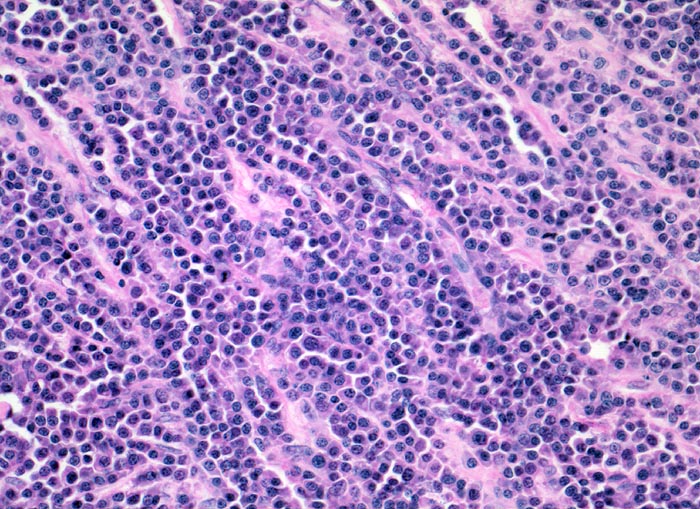

PathoPic – image database / PathoPic ID 4165 - Plasmazellmyelom

Plasmazellmyelom

Die neoplastischen Plasmazellen bilden lockere solide Zellverbände durchzogen von kapillären Gefässen.

Notfalleinweisung wegen umschriebenen Thoraxschmerzen ohne adäquates Trauma. Im Röntgenbild Nachweis multipler Frakturen der Wirbelsäule und der Rippen bei grobsträhniger Osteoporose. In der Serumelektrophorese Nachweis einer Paraproteinämie. Dutcher bodies treten auf bei monoklonaler Immunglobulinproduktion. Sie sind nicht spezifisch für multiple Myelome, sondern können auch beim Morbus Waldenström, lymphoplasmozytischen Lymphomen oder MALT Lymphomen auftreten.

Histologie

200